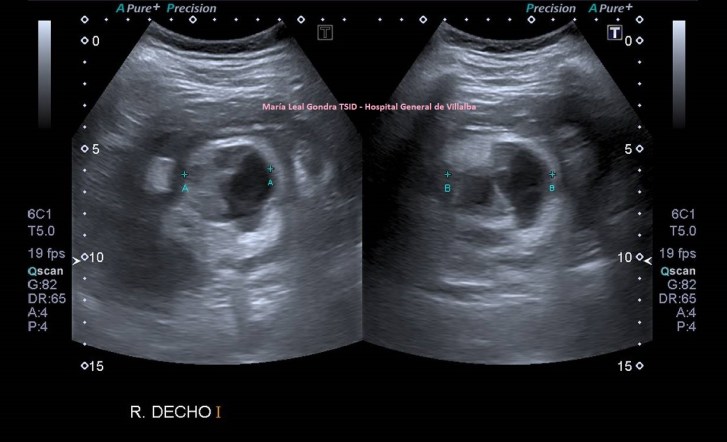

205. Semiología y tumoración renal.

En el post de hoy, desde un oasis, vamos a ver varias imágenes, pero son importantes dos imágenes. De dos personas distintas. Con una lesión en una misma localización anatómica. Una benigna y la otra maligna.

El corte pertenece al polo superior del riñón derecho en el estudio de protocolo de ecografía de abdomen. La conseguimos haciendo este corte:

Este es el modo en el que vamos a colocar el transductor, es un corte longitudinal, donde vemos dibujada la anatomía ecográfica de la imagen 1, de superficial a profundo, piel y tejido celular subcutáneo, inapreciable, pared a abdominal y musculatura superficial, no dibujada, y luego órganos compactos, hígado, riñón derecho, entre ambos, le espacio de Morrison…más profundo el psoas iliaco. El riñón derecho dividido en corteza y seno renal, hipoecogénica e hiperecogénica respectivamente.

En la imagen 1 ves normalidad. La anatomía básica es vital, la semiología que nos habla de isoecogenicidad entre la corteza renal y el parénquima hepático cuando ambos están en situación de normalidad. Esto es básico en esta ecoarquitectura global donde conviven ambos órganos.

En la imagen 2 ves una lesión grande, redonda, de aspecto quístico, anecoica de bordes bien definidos y finos, con buena transmisión de sonido.

2

En la imagen 3,4 y 5 ves una lesión en la misma localización, ecogénica, sólida, heterogénea, redonda y de gran tamaño, lobulada. Tiene vascularización y es heterogénea. Flecha amarilla.

Ambas lesiones ubicadas en el polo superior del riñón derecho. más profundo que el polo inferior, normal, desde el punto de vista ecográfico, según la disposición de la sonda y la situación espacial del riñón en la anatomía humana de modo general, siempre a expensas de rotaciones y variantes de la normalidad.

3

4

5

La semiología nos sirve para identificar lesiones, que la radióloga pueda discernir si éstas, por su aspecto ecográfico, son o no son compatibles con malignidad y en este caso ampliar el estudio si lo considerase oportuno con CT o RMN.

Nos quedamos con la imagen 3 y 4, y en este caso observamos que es una lesión que la paciente ya tenía años atrás y que fue objetivada ecográficamente, de menor tamaño y que en tres años ha crecido considerablemente y que no ha sido tratada durante este tiempo por motivos que desconozco.